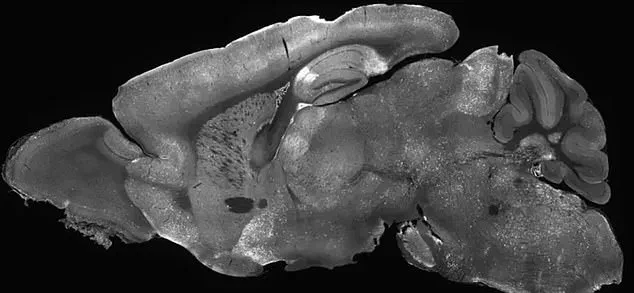

Researchers injected the modified adenoviruses into the cerebral ventricles of mice—the fluid-filled cavities in the brain—using a needle inserted past the eye.

This technique ensured the treatment reached the target areas of the brain.